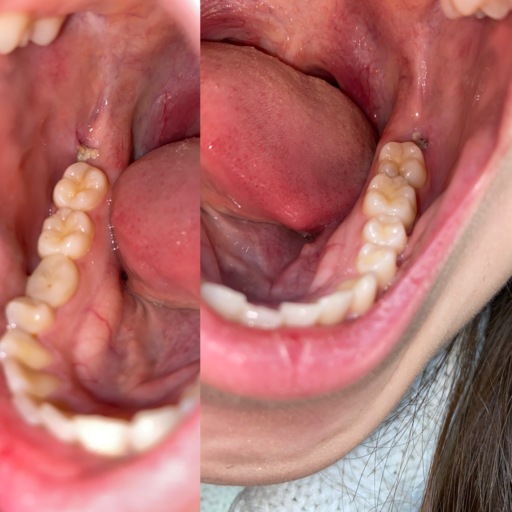

What shall i do with case complain from bone loss and gummy smile ?

case 26 old come to my clinic complain from her smile , after diagnosis is completed Patient suffer from gingival recession with bone loss in upper and lower arch , gingival dept in limited area was 4 , patient had bad history of orthodontic treatment with extraction of 2 upper canines and malaligment of teeth , she complain from pulmonary problems and mouth breather with v shape arch What shall i do in this case